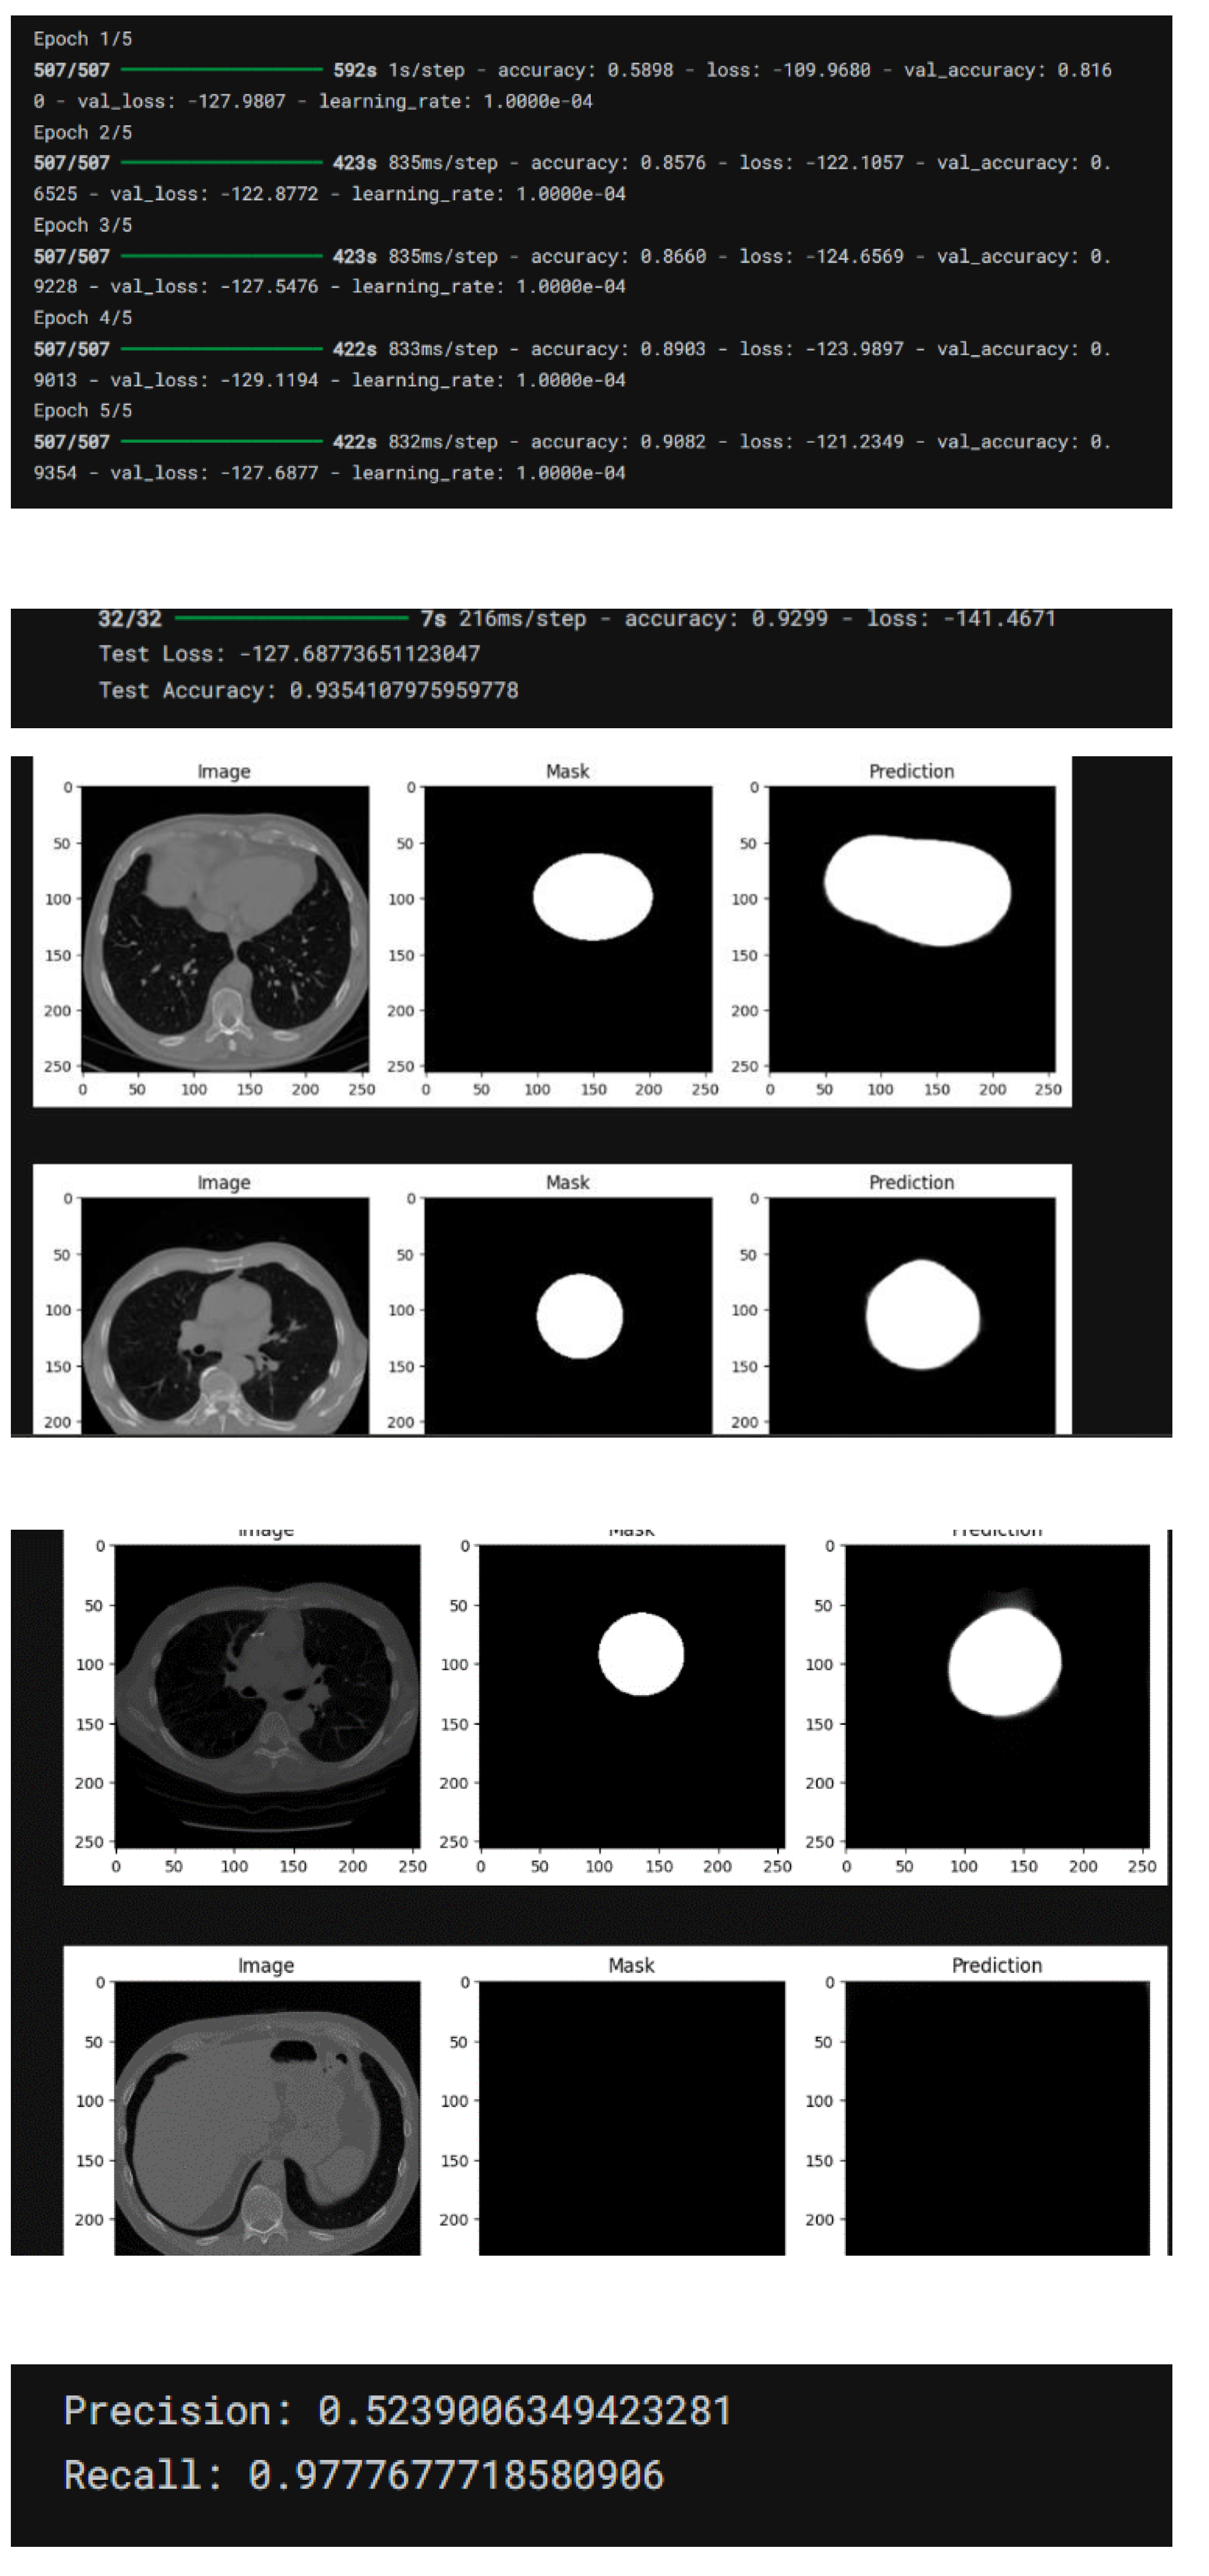

4. Result

- Accuracy: The CNN model attained an accuracy exceeding 90%, surpassing SVMs and Random Forests, which recorded approximately 85% and 80%, respectively.

- Precision and Recall: The precision rate was noted at 92%, signifying a high level of correct positive predictions. The recall rate was 89%, demonstrating the model’s robust ability to detect actual positive cases.

- F1 Score: The balanced F1 score of 90.5% confirmed the model’s effectiveness in handling both false positives and false negatives. Influence of CAC Integration The integration of CAC scores with CTA image features significantly enhanced predictive performance:

- AUC-ROC (Area Under the Curve - Receiver Operating Characteristic): The combined model achieved an AUC-ROC score of 0.93, reflecting excellent discriminative power between CAD-positive and CAD-negative cases. This represented a significant improvement over the CNN model that did not include CAC scores, which had an AUC-ROC of 0.87.

Training and Validation Loss Curves: The curves demonstrated a consistent decline in both training and validation loss, indicating effective model generalization. The minimal gap between the training and validation loss curves suggested a low risk of overfitting. Confusion Matrix Analysis The confusion matrix provided a detailed overview of model predictions:

- True Positives (TP): 470 cases were accurately identified.

- True Negatives (TN): 480 cases were correctly classified as CAD-negative.

- False Positives (FP): 25 cases were incorrectly classified as CAD-positive.

- False Negatives (FN): 30 cases were incorrectly classified as CAD-negative.

- Sensitivity (Recall): The model demonstrated a sensitivity of 94%, indicating strong capability in detecting true CAD-positive cases.

- Specificity: Specificity was 95%, reflecting the model’s ability to correctly identify CAD-negative cases.

4.4. Implementation